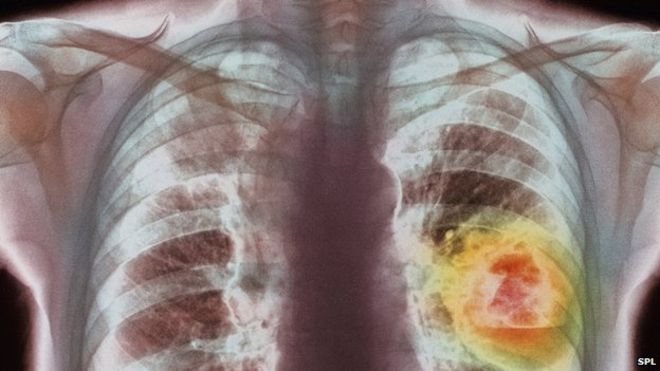

O treime din cazurile de cancer depistate in Romania ar putea fi prevenite printr-o alimentatie sanatoasa si consumul de apa neclorata, sustin specialistii.Un renumit profesor a trecut in vedere evolutia si cauzele maladiilor canceroase, din anii 60.

In Romania sunt aproximativ 480 de mii de bolnavi de cancer. Multe dintre aceste cazuri ar putea fi evitate daca s-ar fi alimentat corect, considera profesorul-doctor Pavel Chirila. Inainte de aparitia industrializarii, mancarea era numai naturala si nimic nu era prelucrat chimic, astfel ca nu se inregistrau cazuri de cancer. O data cu evolutia industriei alimentare, a aparut si incidenta acestei maladii, arata sfatulbatranilor.ro. Fiecare dintre noi, in secolul 21, facem greseli de alimentatie care favorizeaza imbolnavirile. Specialistii au legat evolutioa industrializarii alimentare, inventariind greselile de alimentatie.